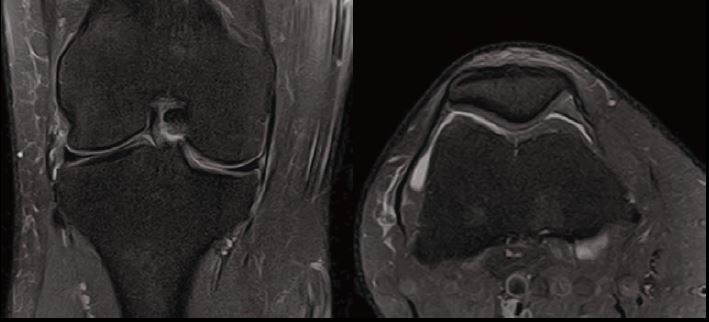

Випадок 1. Велике коліно

Жінка 67 років скаржиться на постійний медіальний біль у коліні.

• Відносно рясний внутрішньосуглобовий випіт.

• Остеоартритне ураження стегново-гомілкового суглоба в медіальній частині зі змінами субхондральної кістки, що може відповідати стресовому перелому.

• Дегенеративна сторона заднього рогу медіального меніска.

Рис. 3 Co FSE PD FS, товщина зрізу 3 мм, роздільна здатність 0,6 мм.

Рис. 4 Axe FSE PD FS, товщина зрізу 3 мм, роздільна здатність 0,6 мм.